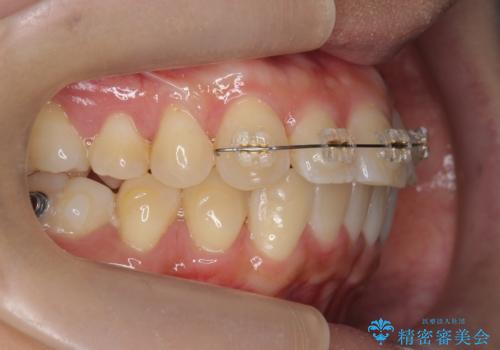

上のワイヤー矯正を半年ほど行い反対咬合を改善してから、上下インビザライン治療を行いました。

下の前歯を中に入れるためにIPR(歯をわずかに削る処置)を行いました。

左上の反対咬合になっていた歯の頬側咬頭は、すでに削れて短くなっていましたがそのまま並べています。